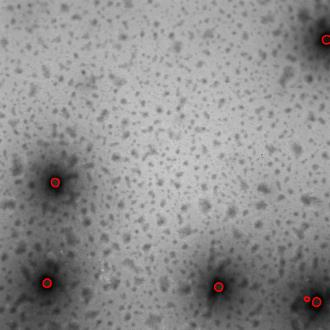

Regular monitoring of the primary particles and purity profiles of a drug product during development and manufacturing processes is essential for manufacturers to avoid product variability and contamination. Transmission electron microscopy (TEM) imaging helps manufacturers predict how changes affect particle characteristics and purity for virus-based gene therapy vector products and intermediates. Since intact particles can characterize efficacious products, it is beneficial to automate the detection of intact adenovirus against a non-intact-viral background mixed with debris, broken, and artefact particles. In the presence of such particles, detecting intact adenoviruses becomes more challenging. To overcome the challenge, due to such a presence, we developed a software tool for semi-automatic annotation and segmentation of adenoviruses and a software tool for automatic segmentation and detection of intact adenoviruses in TEM imaging systems. The developed semi-automatic tool exploited conventional image analysis techniques while the automatic tool was built based on convolutional neural networks and image analysis techniques. Our quantitative and qualitative evaluations showed outstanding true positive detection rates compared to false positive and negative rates where adenoviruses were nicely detected without mistaking them for real debris, broken adenoviruses, and/or staining artefacts.